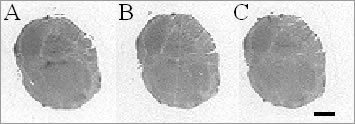

Urotensin-II (U-II) is the most potent constrictor yet discovered (Ames et al., 1999; Maguire et al., 2000). Recent reports documenting increased myocardial expression of U-II and its receptor, UT, in patients with heart failure (Douglas et al., 2002) and increased expression of U-II in human atherosclerosis (Maguire et al., 2004) suggest a potential role for U-II antagonists in human cardiovascular disease. We have determined the ability of a novel, non-peptide U-II antagonist, SB657510 (Douglas et al., 2005), to compete for 125IU-II binding in rat brain and human vascular smooth muscle. Male Sprague-Dawley rats (350-450g) were killed by exposure to increasing concentrations of CO2 followed by exsanguination. Human arteries were obtained, with consent, from patients receiving coronary artery bypass grafts. Cryostat-cut coronal sections (30 µm thick) of rat hind brain and sections (20 µm thick) of human mammary and radial artery were preincubated for 30 min in Tris-HCl (20mM, pH 7.4) containing 5mM MgCl2 and 0.2% BSA. For receptor autoradiography, sections were incubated with 0.25nM 125IU-II (human) for 1h, in the absence (total binding) or presence of the U-II antagonist SB657510 (1 µM). Non-specific binding was determined by inclusion of 10 µM human U-II. The experiment was terminated by 10 min wash in ice-cold Tris-HCl (50mM, pH 7.4). Sections were air-dried and apposed to radiation-sensitive film with 125I standards for 5 days. Receptor binding was analysed using the Quantimet System to determine specific binding density in amol mm-2. Data are mean ± s.e.mean, n values are the number of rats or patients from whom tissue was obtained. Figure 1. Receptor autoradiogram showing 125IU-II binding to the abducens nucleus of rat hind brain in the absence (A) and presence (B) of 1 µM SB657510. Non-specific binding defined by 10 µM U-II (C). Scale bar = 2 mm. High levels of specific 125IU-II binding were detected in the abducens nucleus of rat brain (135.8±5.8 amol mm-2, n=3, Figure 1), with lower levels detected in the medial layer of human mammary (13.0±2.3 amol mm-2, n=3) and radial artery (26.7±8.3 amol mm-2, n=3) as previously reported (Maguire et al., 2000). In rat brain SB657510 (1 µM) competed for 73.1±3.6% (n=3) of the 125IU-II binding in the abducens nucleus and for 73.8±13.1% (n=3) and 66.4±8.0% (n=3) of binding in mammary and radial artery respectively. These data suggest that SB657510 has affinity for both rat and human UT receptors and may be useful in identifying the physiological relevance of U-II, if any, in the human cardiovascular system and its potential contribution to disease.